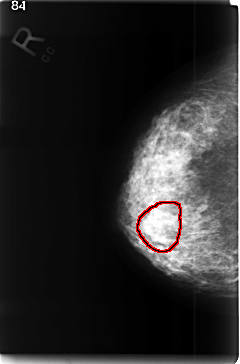

C_0350_1.RIGHT_CC

FILE: C_0350_1.RIGHT_CC.OVERLAY

TOTAL_ABNORMALITIES 1

ABNORMALITY 1

LESION_TYPE MASS SHAPE LOBULATED MARGINS ILL_DEFINED

ASSESSMENT 4

SUBTLETY 3

PATHOLOGY MALIGNANT

TOTAL_OUTLINES 1

BOUNDARY